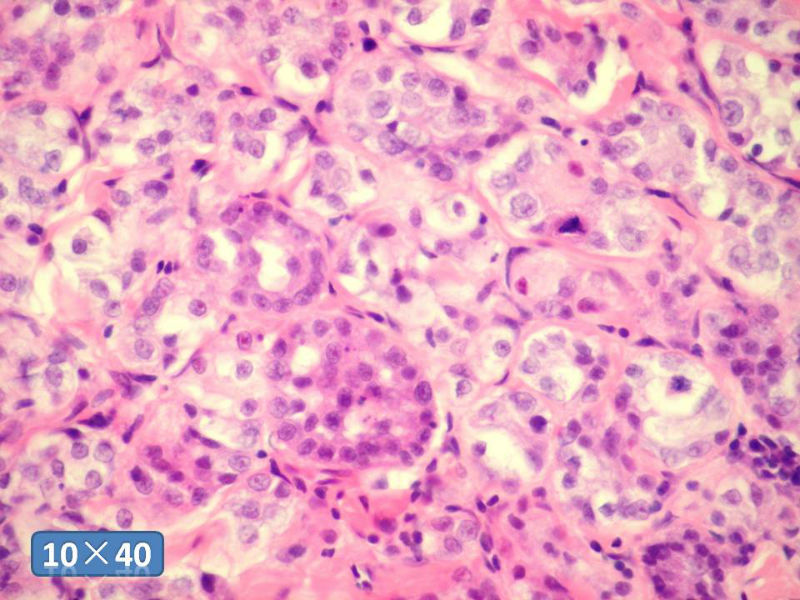

女性,50岁,乳腺肿物,冰冻切片(图1-25)

HE